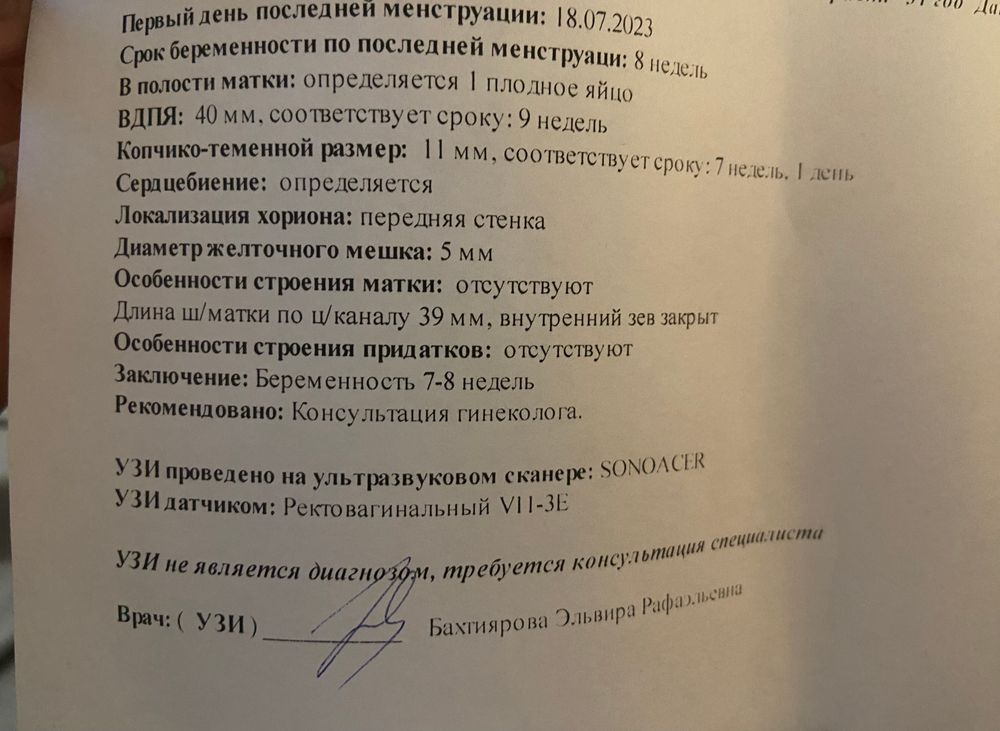

УЗИ, КТГ, доплерСходила я на узи, и все мои переживания улетучились 😭❤️ сердечко бьется и все хорошо, Г сказала что угрозы выкидыша нет единственное размер малыша не соответствует неделям (я это не до конца поняла) но это ничего страшного

когда услышала сердечко малыша расплакалась 😭посоветовала побольше гулять на свежем воздухе и пить больше воды и сказала принимать фолиеваую кислоту (до этого не принимала)